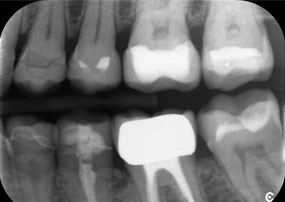

Вторият случай, който подчертава клиничните възможности на Power Edition е свързан с подмяната на увредена циркониева корона при 63-годишна пациентка. Пациентката беше с отчупена фасета на 20-годишната си циркониева корона на зъб 6. Въпреки че дефектът беше в задната област, пациентката намираше дефекта за притеснителен и поиска нова реставрация.

Power Edition позволи прецизно разрязване, като увеличеният въртящ момент и подобреното охлаждане допринесоха за контролираното отстраняване на короната без значителна загуба на материал. Системата на цангата и повишеният въртящ момент се оказаха от съществено значение в този процес.